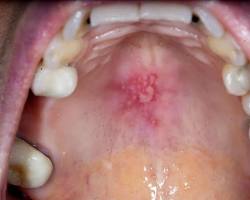

- Oral Thrush:

Oral thrush on the roof of the mouth